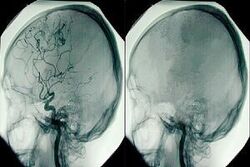

جوان آنلاین: مغز از دو نیمکره به ظاهر هم شکل و به هم متصل تشکیل شده است. بیشتر رشته‌های عصبی مربوط به حرکات بدن انسان از قشر مغز حرکت، در ساقه‌ مغز تقاطع می کنند و دستور حرکت را به اندام‌ها می‌برد.

به گزارش ایسکانیوز، هسته اعصاب دوازده گانه در سیستم عصبی مرکزی قرار دارند و ساقه‌ مغز منشا تنفس، تنظیم فشار خون، و ضربان قلب است.

با اختلال در خونرسانی قشر مغز، تمامی حس و حرکت بیمار از بین می‌رود و تنفس و سایر موارد ذکر شده که از ساقه‌ مغز منشا گرفته است، باقی می‌ماند.

اختلال در خونرسانی به هر دو قسمت قشر مغز و ساقه‌ مغز و تخریب این دو قسمت به صورت برگشت ناپذیر باعث ایجاد شرایطی می شود که به آن مرگ مغزی گفته می شود.

فرد هیچگونه حرکت و ادراکی ندارد، بافت مغز به صورت فراگیر، نابود می‌شود و حالتی بی شکل و برگشت ناپذیر، شبیه به ماست را به خود می‌گیرد. این آسیب برگشت ناپذیر است.

شرح حال بیماری و پرونده بیمار، به دقت بررسی می شود، بیمار از نظر عملکرد اعصاب دوازده گانه ساقه مغزی با وسواس تمام معاینه می‌شود و از بیمار، نوار مغز گرفته می‌شود.